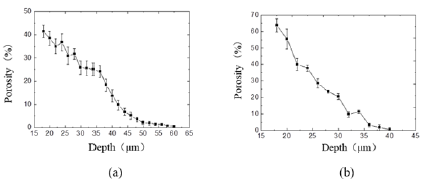

The Dice Coefficient is used to evaluate the similarity between the segmentation result and the real label. Dice Coefficient = 2*predicted correct result/(predicted result + actual result). From Figure 2d, after 119 steps (42 epochs), the IoU is 0.8086, the accuracy acc is 0.9977, and the loss and dice coefficients are 0.101 and 0.8976, respectively, indicating that the model segmentation accuracy is more accurate and the training effect is better 3.3 Porosity of trabecular meshwork. When the TM inner layer was set at 0 μm, the porosity of the TM decreased with its increasing depth (in the flow direction). As shown in Figure 4a, the porosity of the TM with normal IOP was slowly decreased. While under the condition of elevated IOP Figure 4b, it was descending quickly. Additionally, the porosity of the TM in rat eyes with high IOP was less than that in the normal IOP group from the depth of 30 μm to the depth of 60 μm. Under the condition of elevated IOP (7.98 kPa), the porosity of the TM in the superficial region of the TM was rapidly decreasing from 0.65 to 0.31 and decreased from 0.31 (depth 30 μm) to 0.05 (depth 40 μm) in the deeper TM tissue adjacent to the SC. The TM tissue in the high IOP group exhibited the structures of compressed collagen fibres, and the total thickness of the TM decreased compared with the controls. It is indicated that the TM tissue can be collapsed by fusing into surrounding tissues due to the function of elevated IOP. In addition, the findings demonstrated that the changes in the TM tissue in pressurized eyes are large enough to lead to the increased outflow resistance.

Figure 4: Curve of trabecular meshwork porosity with image depth at different intraocular pressures.

a. Under the condition of normal IOP

b. Under the condition of elevated IOP (7.98 kPa).

The meshwork inner layer corresponding to superficial TM was set at 0μm for the calculation of TM porosity.